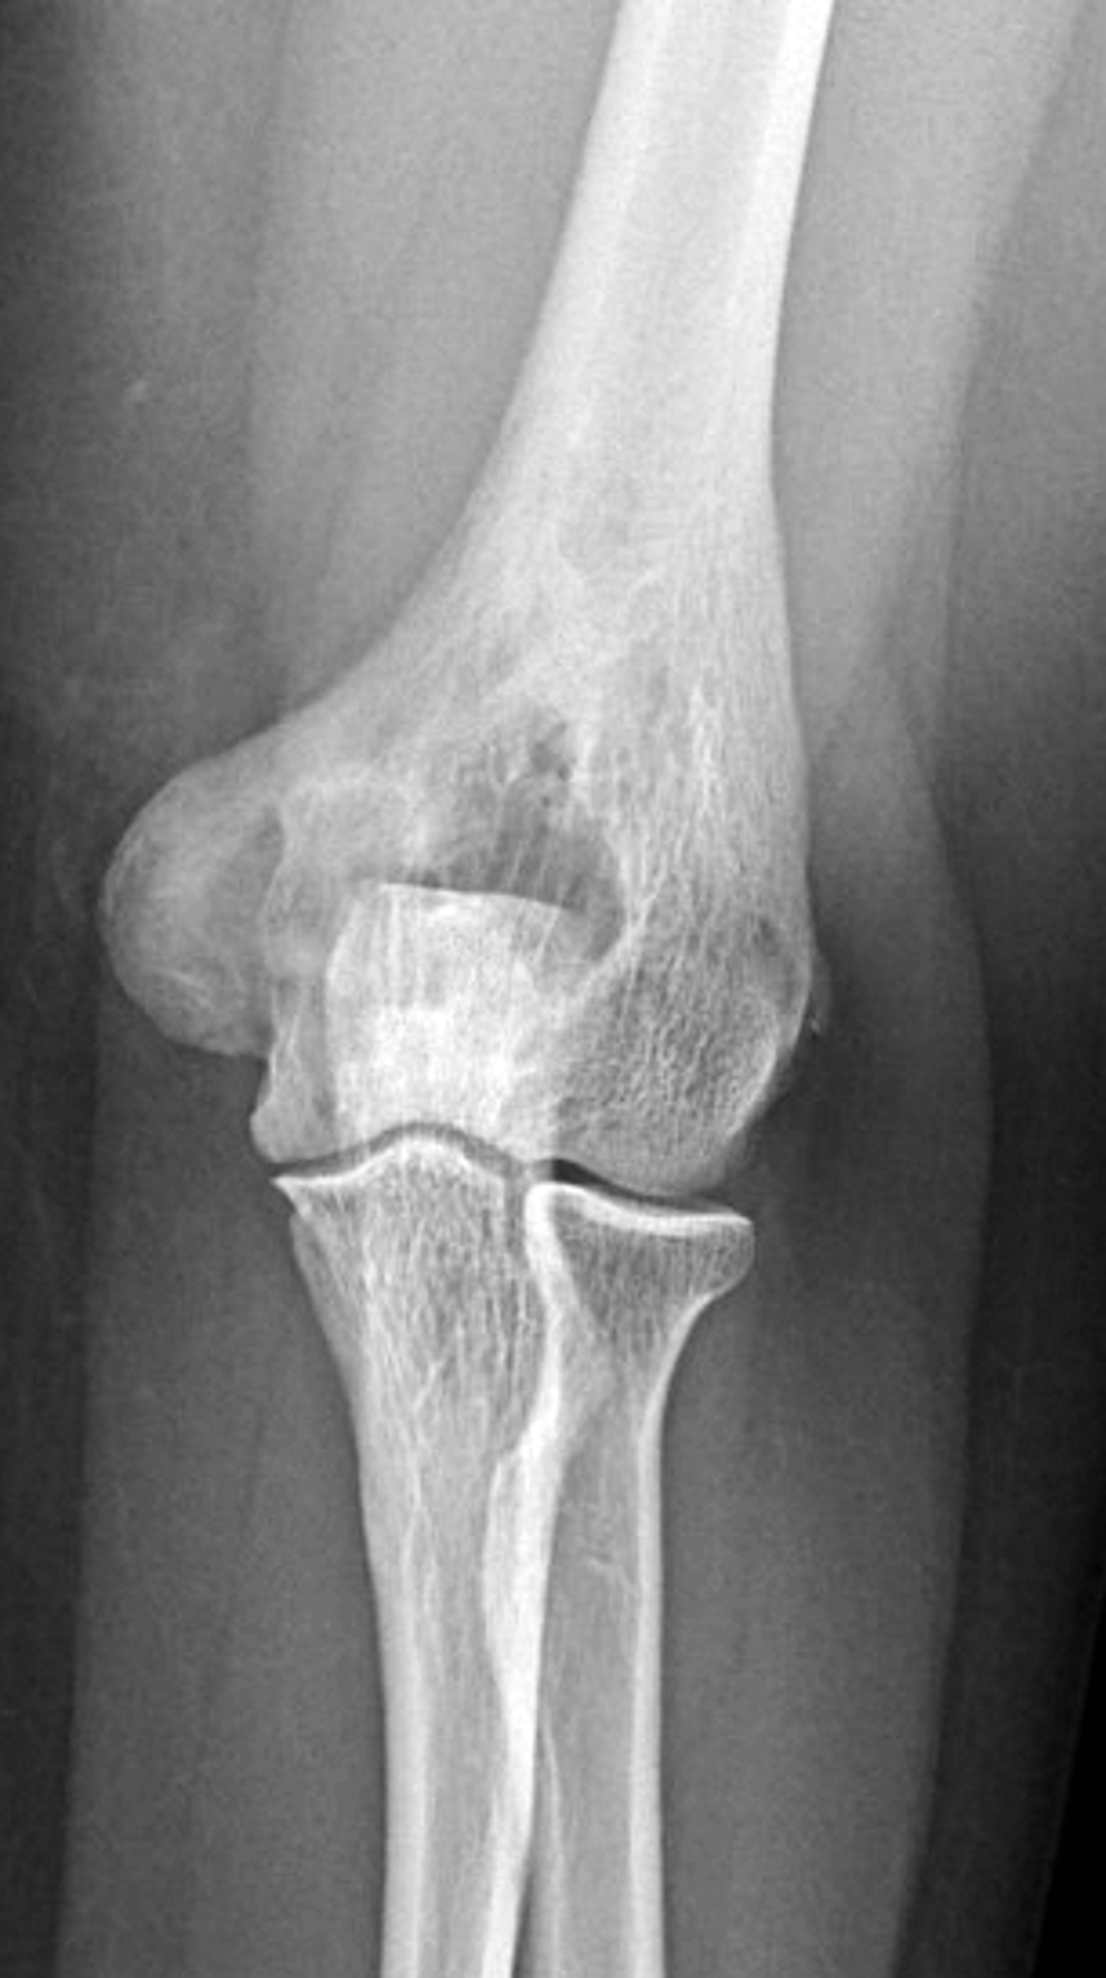

Figure 8: Mixed phase Paget disease in the distal humerus with atypical marrow replacement. (8A) AP and (8B) lateral elbow radiographs show classic findings of Paget disease in the distal humerus, including osseous enlargement, particularly of the medial epicondyle, with associated cortical and trabecular thickening. (8C) T1-weighted and (8D) STIR coronal images show diffusely abnormal marrow signal intensity in the medial humeral epicondyle (asterisks), hypointense compared to skeletal muscle on the T1-weighted sequence and uniformly hyperintense on the STIR sequence. This pattern of marrow replacement is atypical in uncomplicated Paget disease and prompted biopsy, which confirmed the diagnosis. Despite the marrow findings, the radiographic features in addition to the lack of osseous destruction and soft-tissue mass suggest uncomplicated Paget disease and fibrovascular changes. Short interval follow-up to document stability may obviate the need for biopsy in similar cases.